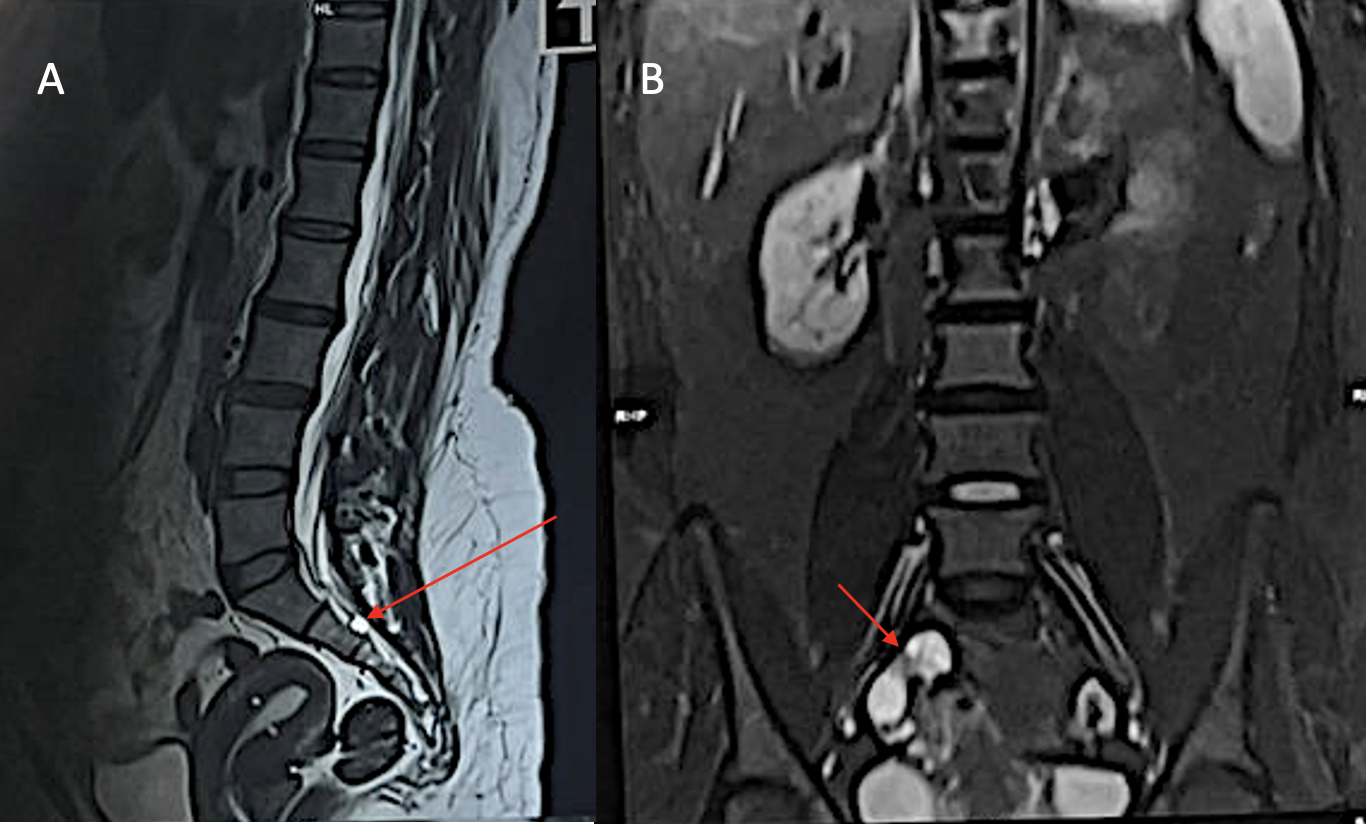

A 31-year-old nulliparous female presented with a 1-year history of sharp, burning pain localized to the right vulvar region, radiating to the perianal area and posterior thigh. The pain was spontaneous in onset, exacerbated by sitting and prolonged standing and significantly interfered with her daily routine, particularly her ability to engage in sexual activity. There was no history of recent trauma, infection or dermatologic lesions. Multiple prior therapeutic trials, including antifungals, topical steroids, tricyclic antidepressants and Gabapentinoids, offered minimal relief. On clinical examination, the vulvar skin appeared normal, without signs of inflammation or dermatologic pathology. Digital rectal examination revealed localized tenderness over the right ischial spine, suggestive of pudendal nerve irritation. There was no evidence of pelvic organ prolapse, perianal anesthesia or anal sphincter laxity. Her pelvic floor distress inventory-20 (PFDI-20) score was 7.13/300, consistent with minimal distress at presentation. The radiographs were unremarkable (Fig. 1). MRI of the lumbo-sacral spine, including T1-weighted, T2-weighted and short tau inversion recovery sequences, revealed a well-defined perineural (Tarlov) cyst measuring 1.7 × 1.2 × 1.3 cm at the right S2 neural foramen, with displacement and compression of the adjacent S2 nerve root. Mild disc bulges were also noted at L2-L3 and L3-L4 levels (Fig. 2). The lesion was classified as a Type II perineural cyst per Nabor’s classification and no other spinal abnormalities were detected. A diagnosis of neurogenic vulvodynia secondary to S2 nerve root irritation from the Tarlov cyst was established.

Figure 2: Magnetic resonance imaging showing the Tarlov cyst in T2-weighted sagittal view (a) and the cyst arising from the foramen seen in T2-weighted coronal view (b).